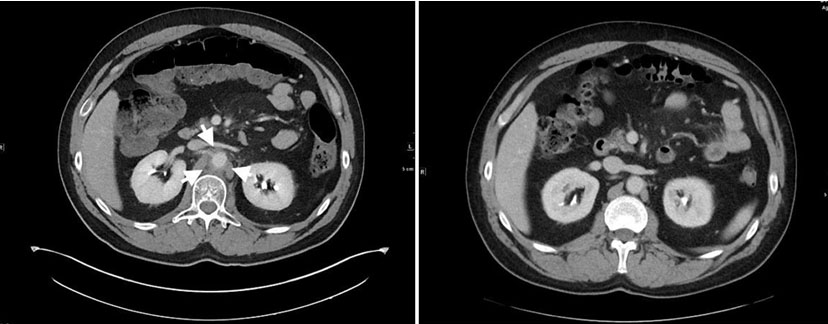

This is a man who presented in April 2017 with left upper quadrant abdominal pain. Computed tomography (CT) of the abdomen showed a mass in the tail of the pancreas and diffuse liver metastases. Pathology from the liver biopsy showed a high-grade neuroendocrine cancer with numerous mitotic figures and apoptotic bodies, and Ki-67 proliferation index of 90%. Chest CT was negative. The patient’s tumor underwent genomic analysis in May 2017 utilizing FoundationOne, a next-generation sequencing (NGS) based assay. The assay performed on his sample interrogated 315 genes as well as introns of 28 genes involved in rearrangements. Genomic alternations identified in his sample included RB1 loss exons 18–27 and GABRA6 V2281. The patient received 7 cycles of carboplatin and etoposide and obtained a complete radiographic response. In October 2018 he developed a recurrence in the liver and was retreated with carboplatin and etoposide with the addition of the PD-L1 inhibitor atezolizumab. After two cycles of therapy, administered at 21-day intervals, he developed abdominal pain. Computed tomography scan showed inflammation and stranding around the aorta consistent with aortitis. Prednisone was initiated, 1 mg/kg and the pain resolved within a week. He continued treatment on chemotherapy alone while receiving a 2-month prednisone taper. After 6 cycles of chemotherapy, he again achieved a remission. Three months after discontinuation of therapy he recurred with diffuse liver metastases. Atezolizumab was reinitiated with carboplatin and etoposide. After two cycles, he again developed severe abdominal pain. Computed tomography scan (Figure 1) showed interval development of significant inflammatory fat stranding and soft tissue thickening about the abdominal aorta, most notably at the level of the renal arteries. Inflammatory stranding extends along the spinal muscular atrophy (SMA) (Figure 2), consistent with recurrence of aortitis. Steroids were instituted and the aortitis resolved. The patient had subsequent recurrences bud did not respond to treatment with topotecan and subsequent treatment with lutetium Lu 177 dotatate. In December 2020, he had continued disease progression. Treatment with cisplatin, etoposide, and the PD-1 inhibitor pembrolizumab was started. He has had 6 cycles of combined chemoimmunotherapy without recurrence of aortitis and had a partial remission.

Figure 1: Inflammation around the abdominal aorta (left) and resolution after two months of corticosteroids (right).